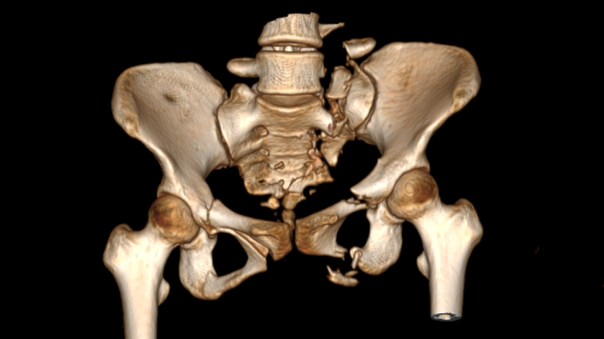

据悉,该患者有着骨盆多发性骨折(Tile C1.3型)、胸腰椎多发骨折并不全瘫,肾、脾挫伤。骨盆骨折,是最严重的骨创伤,常伴随大量失血以及其他脏器损伤,致死(8%-37%)致残(60%)率居所有骨折首位。手术治疗难度大、风险高,一直是创伤骨科领域公认的难点。传统切开复位内固定手术耗人耗时,对患者损伤大,更大几率导致大出血。即便如此,仍有不少患者无法达到满意的骨盆复位,最终留有残疾。

图二:患者术前影像资料

该患者为年轻女性,伤势严重且伤后等待救治时间较长(伤后13天接受手术),除了骨盆骨折之外,还合并胸腰椎多发骨折并不全瘫,肾、脾挫伤。若采用传统术式,损伤较大,且需要分期治疗骨盆骨折及腰椎骨折,同时还有继发脏器出血的风险。副院长孙涛、东院创伤一科主任洪焕玉及其团队反复讨论后决定实施创新术式,采用目前全球最先进的“智能化骨科手术机器人全流程辅助骨盆骨折闭合复位内固定手术”治疗方式。